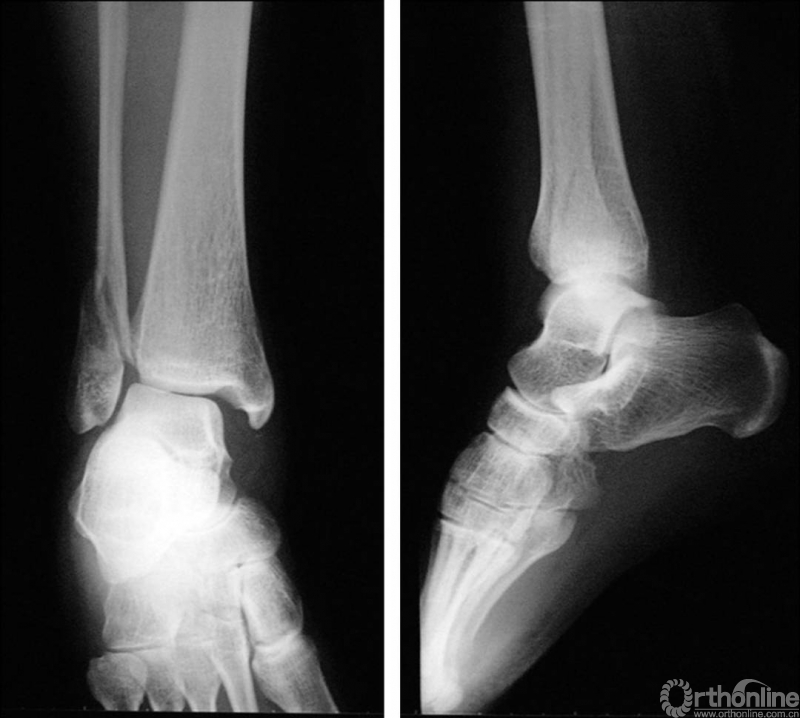

X线诊断:标准的踝关节影像学评估应包括3个位相:前后位(图5),踝穴位(内旋15°)(图6),侧位(图7)。

图5 前后位

图6 踝穴位(内旋15°)

当踝关节严重损伤时内外踝及距骨将发生不同程度的移位(图8)。有时外踝骨折会伴有三角韧带的损伤,静态的X线摄片并不能准确地反映踝关节的稳定性,应力位片及MRI检查可完善对踝关节稳定性及韧带损伤的评估(图9)。此时应通过患肢损伤机制及放射资料准确判断踝关节损伤的类型以正确指导复位和固定。有时单纯内踝骨折可能是更为复杂的“Maisonneuve骨折”的一部分,该骨折还包括腓骨近端骨折及韧带联合损伤,故X线检查应投照整个胫腓骨。